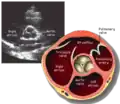

Parasternal short axis (PSAX)

This view is obtained in the same window as the parasternal long, but with the probe rotated 90°. In this view, the aortic valve is seen in cross-section with the right ventricular inflow & outflow tracts visible with the tricuspid valve as well. Pulmonary valve is not visible in this view. Both the right and left atria are visible.

The standard PSAX view is at the level of the aortic valve, but moving the probe along the long-axis can review the LV outflow tract, LV at the base, and LV at the midsection.

Structures visible:

- Aortic valve in short-axis

- Aortic valve dysfunction, aortic sclerosis/stenosis

- Tricuspid valve in long-axis

- Pulmonary valve in long-axis

- Right ventricle, including inflow and outflow tracts

- Left ventricle in short-axis